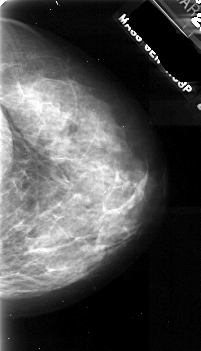

A_1047_1.RIGHT_MLO

RIGHT_CC LINES 4906 PIXELS_PER_LINE 2806 BITS_PER_PIXEL 16 RESOLUTION 42 NON_OVERLAY